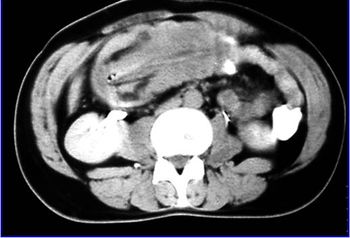

Patient swallows multiple foreign bodies.